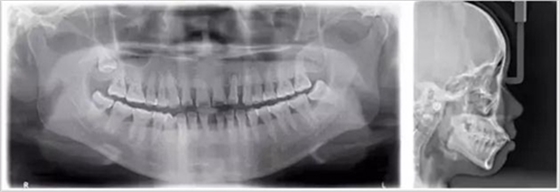

牙齒的牙根是埋在牙槽骨中的,醫(yī)生沒有透視眼,為了解患牙的牙根的形態(tài)、走向、長度及根尖周有無病變及病變大小,或者懷疑有肉眼無法確認(rèn)的其它牙科問題,都會建議患者去牙科的X光,甚至,口腔CT來全面性地確認(rèn)問題,以訂定合適的治療計(jì)劃。

美國牙醫(yī)協(xié)會也給出數(shù)據(jù),在醫(yī)療輻射中,來源于牙科的輻射僅占到約2.5%。關(guān)于牙科放射量,兒童放射學(xué)會給出更為清晰的對比:拍一張曲面平展的輻射量,相當(dāng)于約3天的自然環(huán)境輻射量;4張牙合翼片的輻射相當(dāng)于約0.6天的自然環(huán)境輻射量??傊?,拍牙片的輻射量其實(shí)是較小,大家不用擔(dān)心。